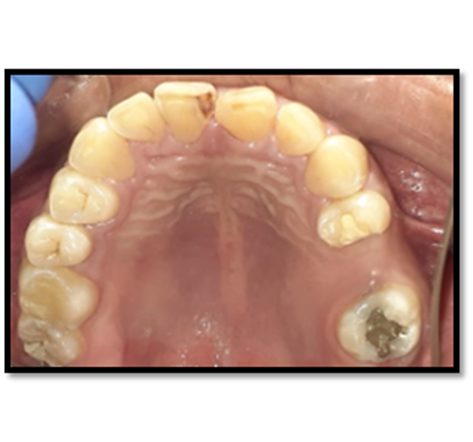

El estudio radiográfico puede evidenciar múltiples sombras radiopacas rodeadas de un halo radiolúcido pertenecientes a un tumor odontogénico CIE10: D164 (odontoma compuesto), localizados en a nivel de los órganos dentarios 4.3; 4.1; 3.1; 3.2; 3.3. También se puede constatar la presencia de una sombra radiopaca que concuerdan con el órgano dentario retenido.

Imagen 2. Radiografica Panorámica.

El órgano dentario retenido tiene una dirección mesioangular, sobrepasando la corona la mitad de la línea media. En íntima relación se encuentra las raíces de los órganos dentarios 4.1; 3.1; 3.2 con los dentículos y adicionándose con la relación del órgano dentario retenido esta la raíz del órgano dentario.

Imagen 3. Radiograficas Peiapical.

Los resultados de los exámenes radiográficos evidencian que se trata un odontoma compuesto que se confirmara con el estudio histopatológico posquirúrgico.

El diagnóstico y tratamiento oportuno que se debe tener frente a las neoplasias odontogénicas que son frecuentes en la consulta odontológica, y la mayoría de casos pasa desapercibido nos hacen tomar conciencia de lo importante de tratar , guiar a los pacientes que visitan la unidad de atención odontológica Uniandes a realizarse exámenes complementarios, radiográficos panorámicos, periapicales, oclusales que tienen la posibilidad de demostrar una visión más clara de las estructuras dentarias vecinas, previniendo desarrollos o formaciones de neoplasias ya que, las radiografías las intraorales periapicales, oclusales demuestra mayor fidelidad dimensional en comparación a la panorámica detectando oportunamente patologías que son asintomáticas.

En su gran mayoría en la presentación de este caso clínico se puede observar la presencia de una sombra radiopaca que concuerdan con el órgano dentario retenido 4.2.con una imagen mixta con múltiples radiopacidades muy similares a los órganos dentarios que están rodeados de un halo radiolúcido perimetral que son similares descripciones de investigaciones de otros autores.